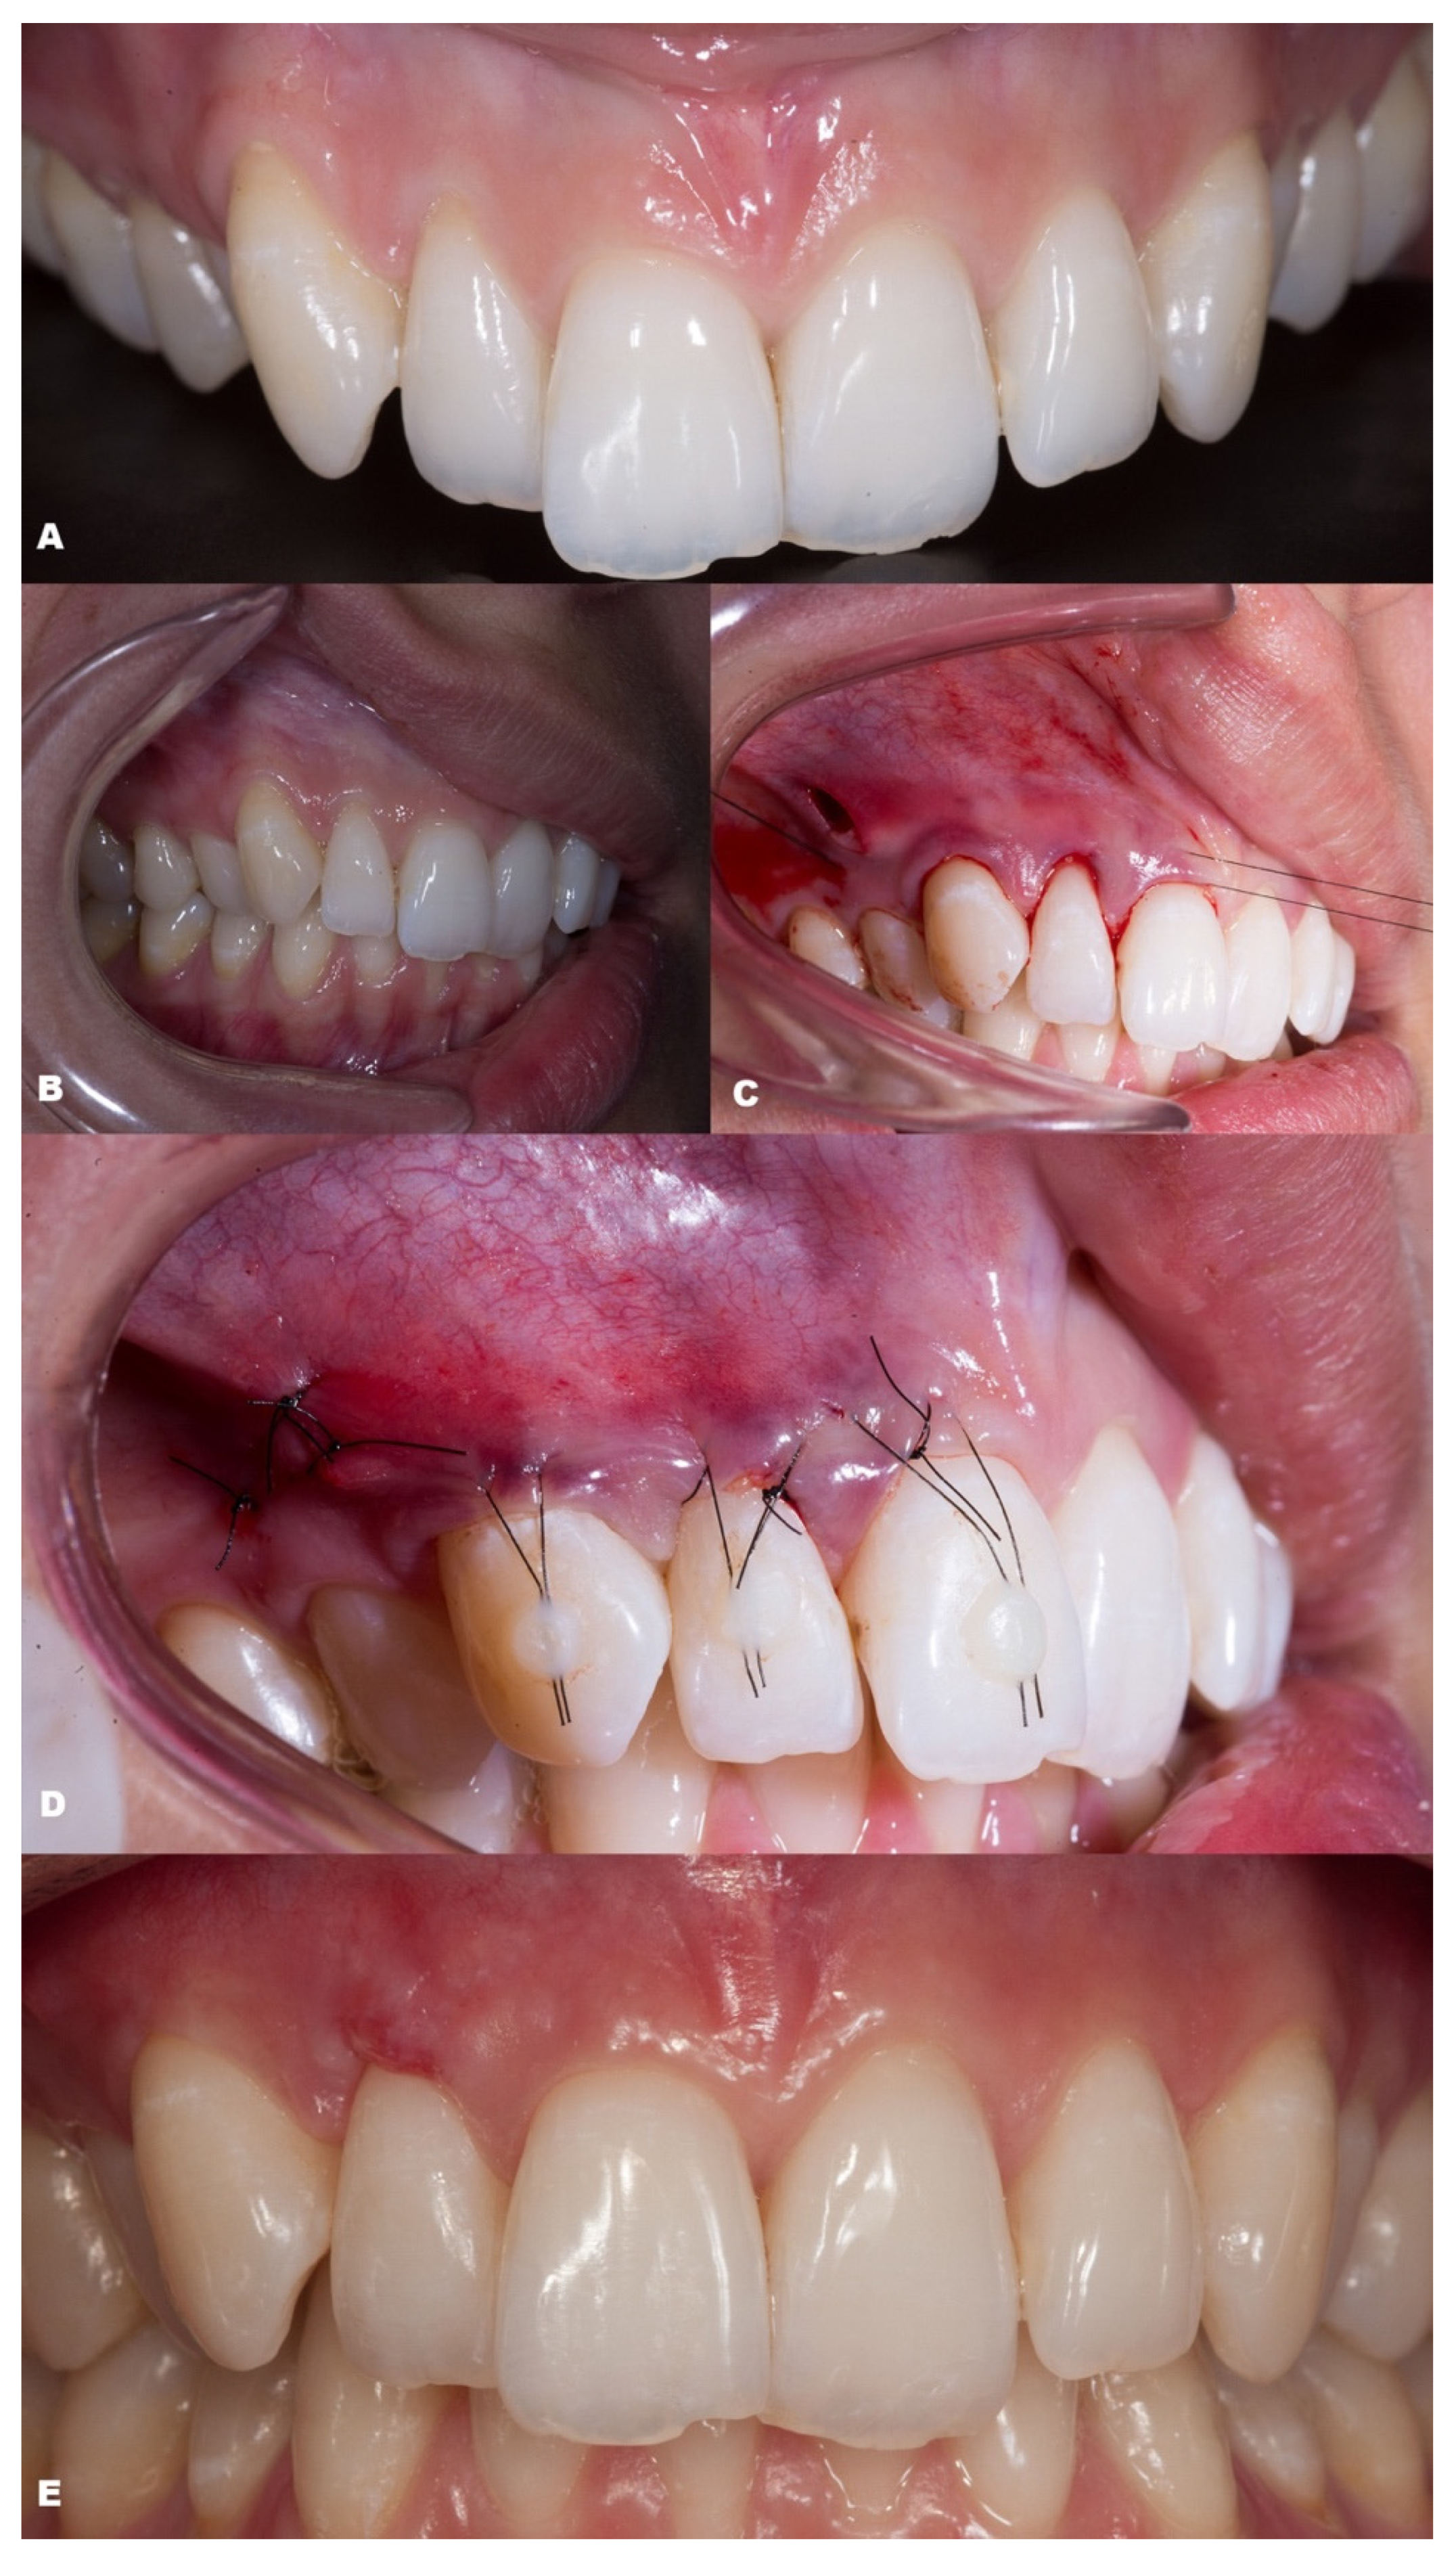

| Classification | Gender | Tooth/Teeth with REC | Initial REC Height (mm) | Initial REC Width (mm) | Initial PD (mm) | Initial KTW (mm) | Final REC Height (mm) | Final PD (mm) | Final KTW (mm) | % RC | p-Value | |

|---|---|---|---|---|---|---|---|---|---|---|---|---|

| Baseline | 6-Month Follow-up | |||||||||||

| Case 7 | RT1 | F | 12 11 21 22 | 1.1 1.5 2.4 1.5 | 1.5 3.0 4.0 2.0 | 1.0 2.0 1.5 2.0 | 5.4 5.0 6.3 6.9 | none | 1.0 2.5 2.5 1.5 | 4.3 5.7 6.0 6.3 | 100 100 100 100 | |

| Case 8 | RT2 | F | 42 41 31 32 | 2.2 3.4 3.2 1.2 | 2.3 2.5 3.0 2.7 | 0.5 0.5 0.5 1.0 | 2.4 1.9 1.5 3.5 | 0 0.6 0.6 0.5 | 1.5 1.0 1.0 1.0 | 3.6 2.9 2.1 3.3 | 100 82.35 81.25 58.34 | |

| Case 9 | RT1 | F | 12 13 | 1.3 2.1 | 2.2 2.3 | 1.5 2.0 | 4.4 5.3 | none | 2.5 1.5 | 4.6 5.2 | 100 100 | |